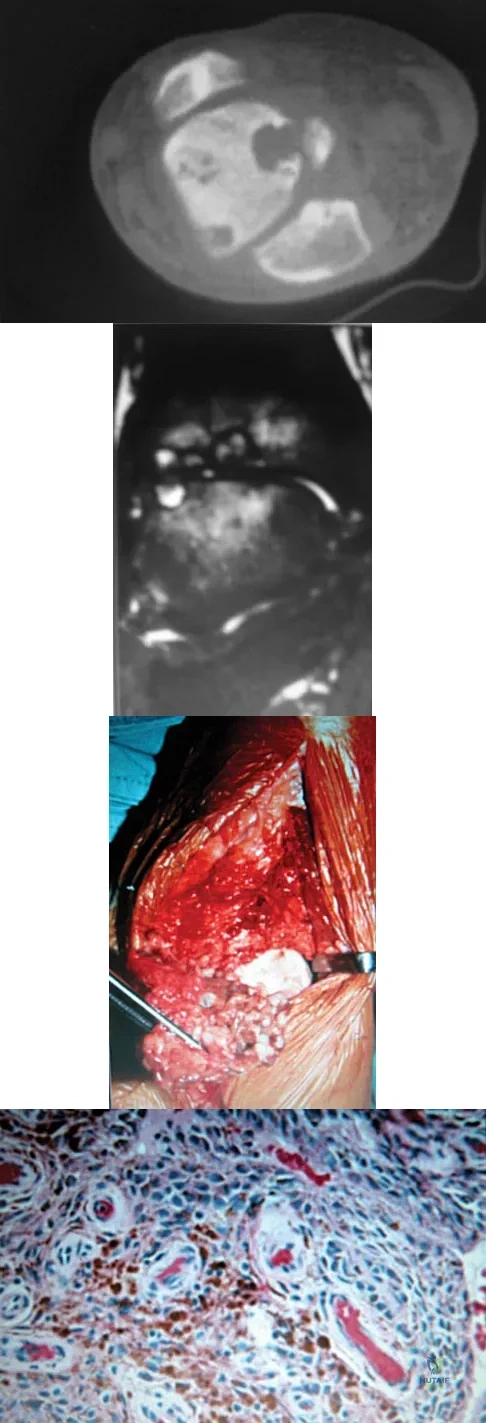

A 30-year-old man has had intermittent swelling of his right ankle for the past 6 months. He denies any history of trauma. Radiographs reveal osteolytic changes on both sides of the joint. An axial CT scan and a T2-weighted MRI scan are shown in Figures 40a and 40b. He undergoes surgical excision. An intraoperative photograph and a biopsy specimen are shown in Figures 40c and 40d. What is the most likely diagnosis?